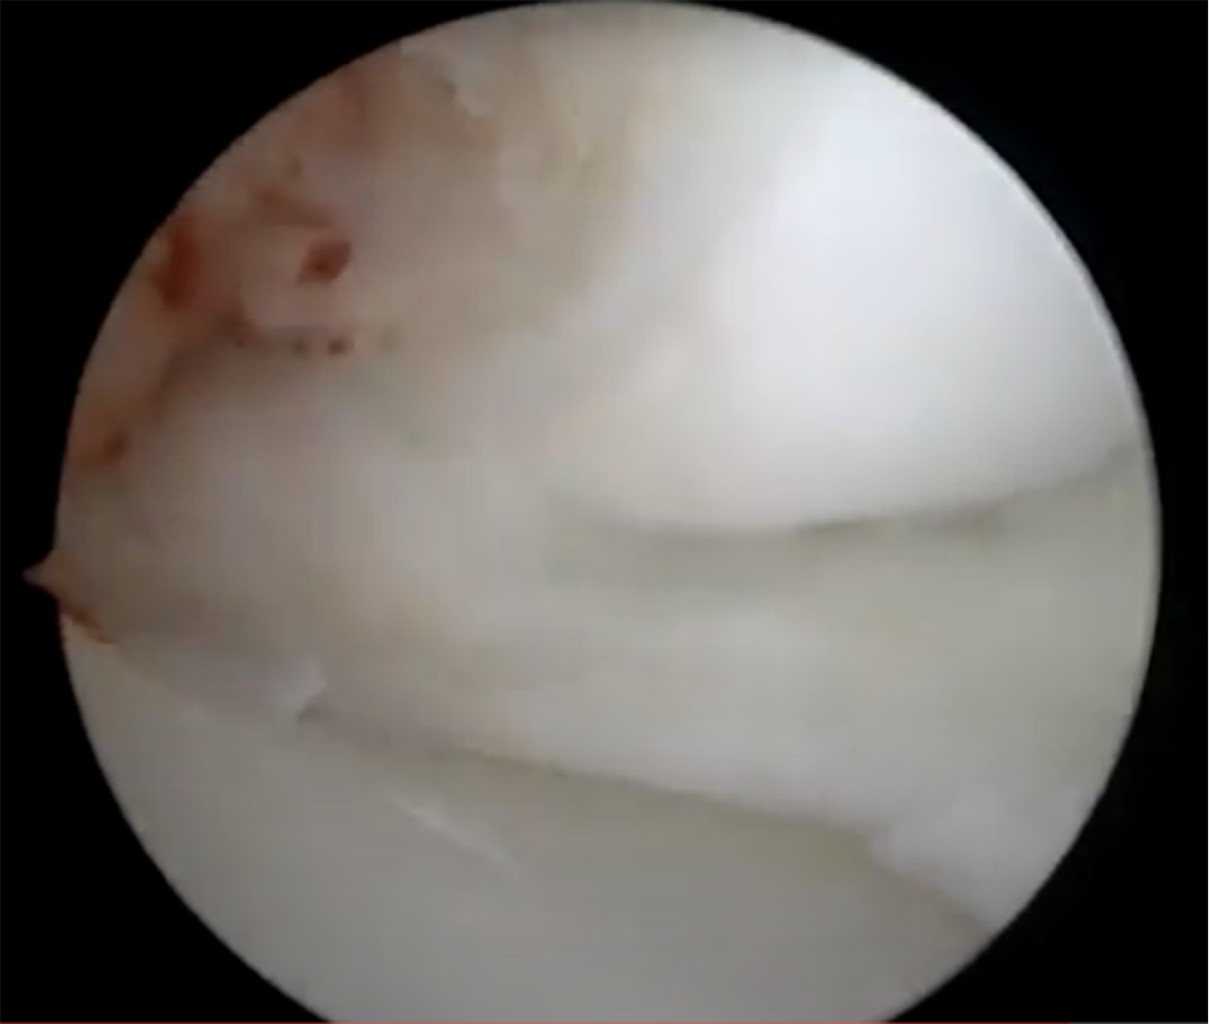

Durante la artroscopía de la rodilla derecha, se encontró una lesión compleja en el menisco medial, que fue diagnosticada como un menisco discoide. Además, se observó una abundante sinovitis y Hoffitis, así como la presencia de una banda fibrosa en la parte ventromedial (Figuras 3 y 4). Se realizó una plastía del menisco medial mediante saucerización y se determinó que el menisco medial estaba estable, por lo que no se requirió el uso de suturas meniscales (Figuras 5, 6 y 7). También se realizó la resección de la banda fibrosa, sinovectomía y Hoffectomía.

Figura 4

Figura 5

Figura 6

Figura 7